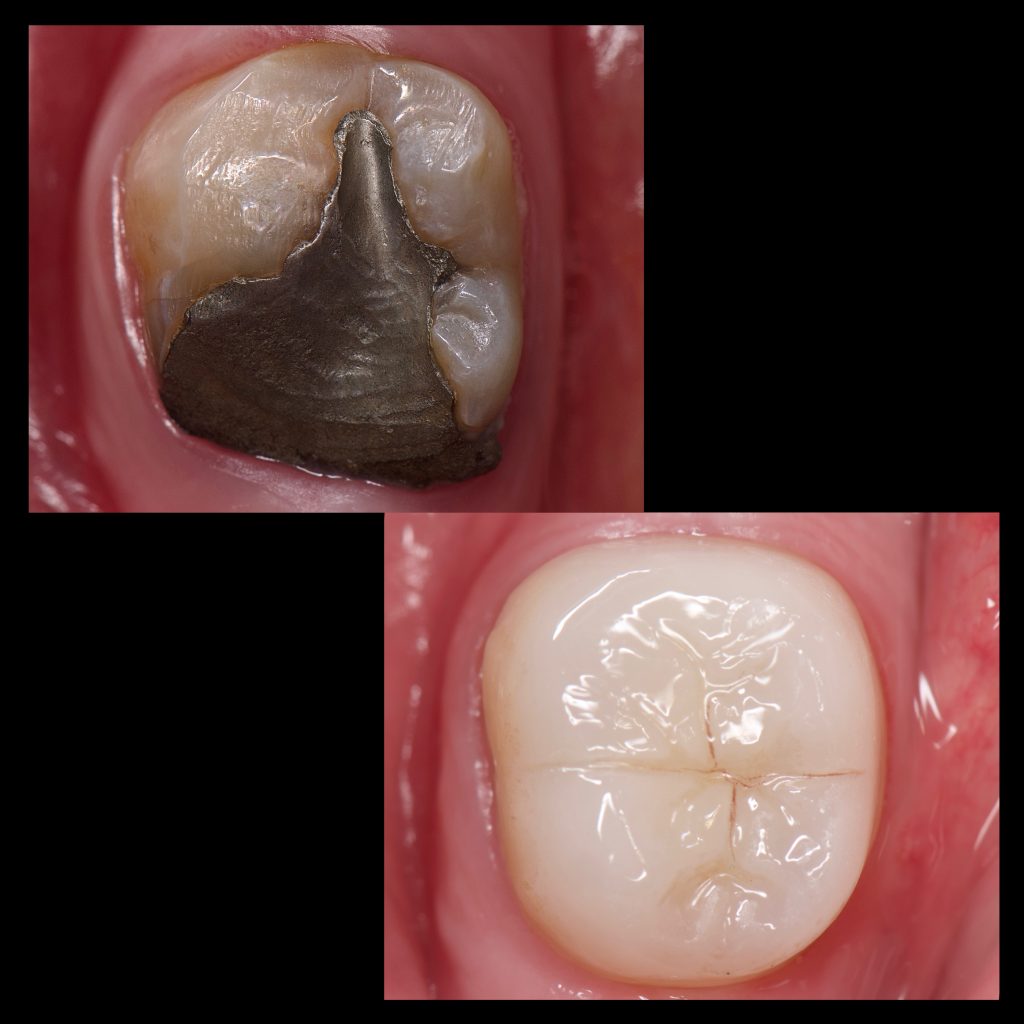

– Sandblasting, Se clearfil Bond , Resin coating, Ever X as dentine replacement And direct composite restoration to complete the biobase

– Circumferential preparation done because the remaining enamel was carious mesially and demineralised buccally and lingually

– E max crown bonded with Heated Ap-x composite

– Follow up after 3 months